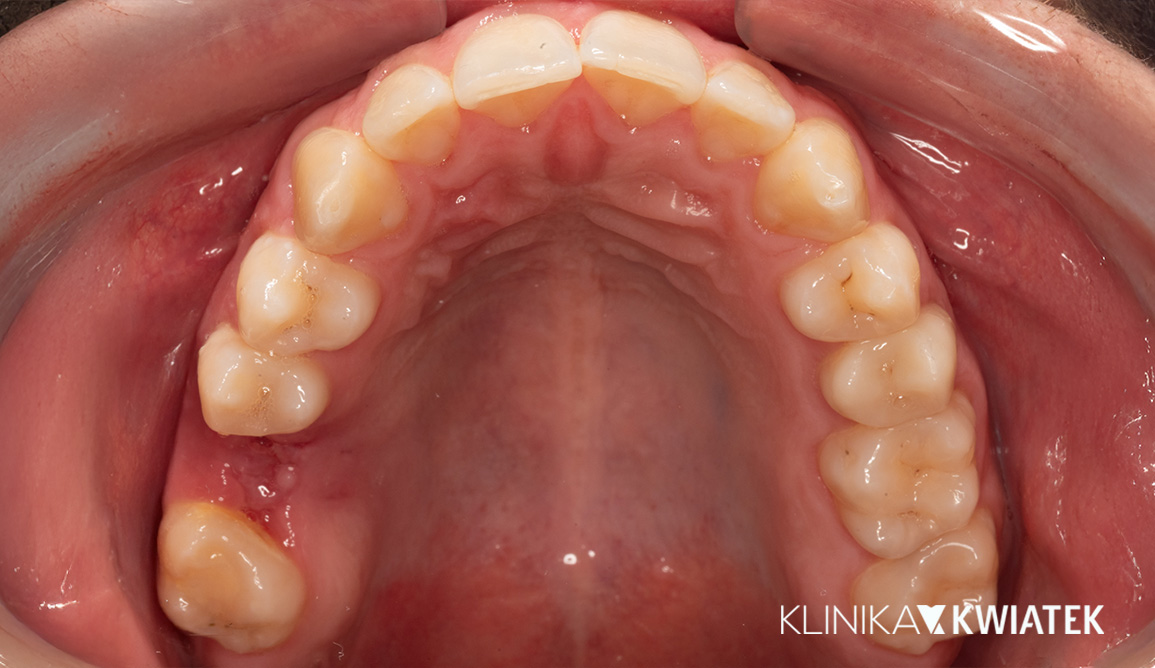

Kompleksowa metamorfoza uśmiechu – od ortodoncji po protetykę i implantologię

Pacjent zgłosił się do kliniki z problemem przetrwałych zębów mlecznych, diastemy i nierównego zgryzu, oczekując szybkiego, ale trwałego efektu estetycznego. Przeprowadzono wieloetapowe leczenie obejmujące higienizację, leczenie zachowawcze, terapię nakładkami ortodontycznymi, implantację oraz nowoczesną protetykę. Finalnym efektem jest harmonijny, biały i zdrowy uśmiech, dopasowany do rysów twarzy.